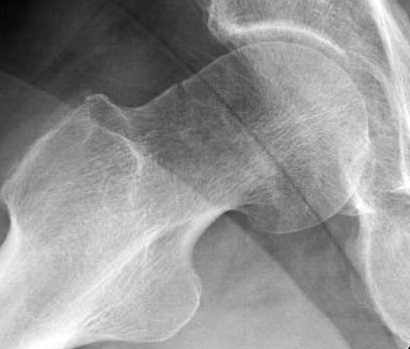

Почему неполный перелом? Я бы назвал его вколоченным!

Перелом конечно не вколоченный т.к. видно линию перелома и нет суперпозиции костной ткани.

Добрый день. Перелом коварный. Через время может произойти лизис в области "неполного" перелома и он превратиться в "полный" со всеми очевидными проблемами, тем более у пациента, склонного к питию. Если не разовьется делирий или после выхода из него, рекомендую внутренний остеосинтез винтами.

Профилактику дальнейшего раскола неполного перелома шейки провели тремя канюлированными шурупами.